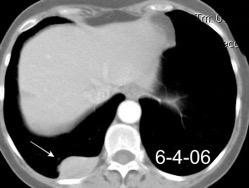

Hemorrágica………….30-70 UH

Extravasación iv. con sangrado activo……….>90 UH

“Simpático”………….,,,,<15 UH

Durso AM et al. Penetrating Thoracic Injury. Radiol Clin N Am 2015.

Urogénico……………….< 15 UH

Entérico.. ………………+/- 15UH

Biliar, Quiloso……………..<0 UH

Urinoma

Hemotórax

Quilotórax

Absceso pared en empiema Tb

Derrame no complicado + hematoma mediastínico

68 UH

Empiema pleural post-trauma

12UH

Abramowitz1 Y et al. Pleural Effusion: Characterization with CT Attenuation Values and CT Appearance .AJR 2008